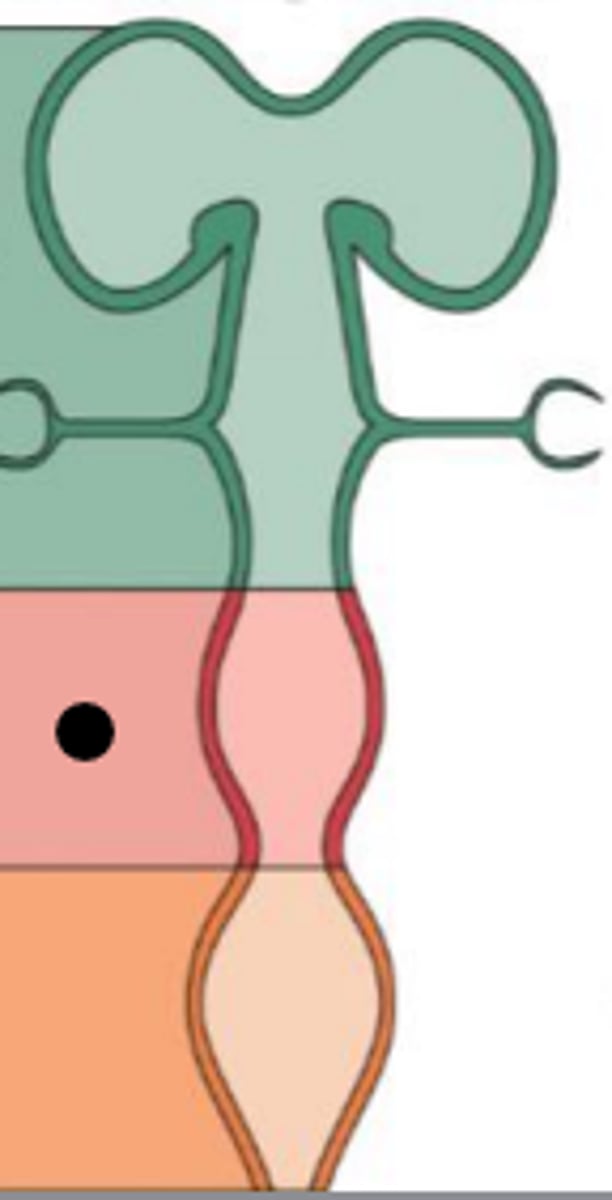

What is the main name of the pink area?

Name one structure that comes from it?

What structure is the arrow pointing to?

What structure is the red arrow pointing to?

Which structure is the blue arrow pointing to?

What region does the orange X represent?

What area is the orange structure pointing to?